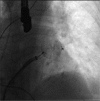

Atrial fibrillation (AF), the most common cardiac arrhythmia, confers a 5-fold risk of stroke that increases to 17-fold when associated with mitral stenosis. At this time, the most effective long-term solution to protect patients from stroke and thromboembolism is oral anticoagulation, either with vitamin K antagonists (VKAs) or a novel oral anticoagulant (NOAC). Despite the significant benefits they confer, both VKAs and NOACs are underused because of their increased potential for bleeding, and VKAs are underused because of their narrow therapeutic range, need for regular international normalized ratio checks, and interactions with food or medications. In patients with nonvalvular AF, approximately 90% of strokes originate from the left atrial appendage (LAA); in patients with rheumatic mitral valve disease, many patients (60%) have strokes that originate from the left atrium itself. Surgical LAA amputation or closure, although widely used to reduce stroke risk in association with cardiac surgery, is not currently performed as a stand-alone operation for stroke risk reduction because of its invasiveness. Percutaneous LAA closure, as an alternative to anticoagulation, has been increasingly used during the last decade in an effort to reduce stroke risk in nonvalvular AF. Several devices have been introduced during this time, of which one has demonstrated noninferiority compared with warfarin in a randomized controlled trial. This review describes the available technologies for percutaneous LAA closure, as well as a summary of the published trials concerning their safety and efficacy in reducing stroke risk in AF.